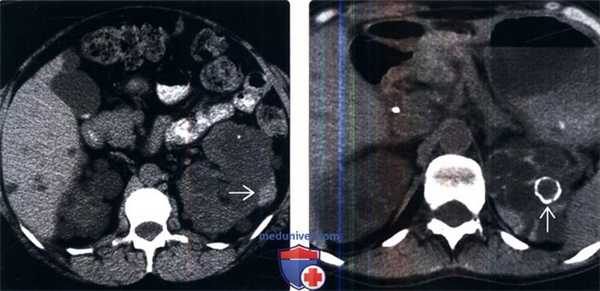

(Слева) КТ с контрастированием у пациента с аутосомно-доминантной поликистозной болезнью почек, аксиальная проекция: множественные двусторонние простые кисты почек. Стенки кист плохо различимы, не накапливают контраст.

(Справа) УЗИ, продольная плоскость сканирования: у этого же пациента обнаружены множественные простые анэхогенные кисты в увеличенной правой почке. Для данного заболевания характерно прогрессирующее увеличение объема кист и почки.г) Патология: